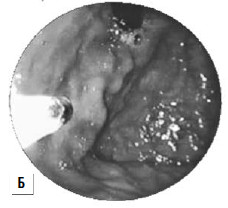

При интенсивном кровотечении, когда невозможно найти участок с нарушенной стенкой вены, при тяжелом состоянии больного показана постановка зонда Блэйкмора (с его установки и следует начинать лечение в большинстве случаев, так как эндоскопический гемостаз пока возможен не во всех учреждениях, да и в ночное время может не быть нужного специалиста и соответствующего технического обеспечения, а, кроме того, эндоскопический гемостаз на высоте кровотечения может быть технически невыполним, так как кровь будет заливать оптику). Эффективность метода достигает 85 %, а количество рецидивов – 50 % (рис. 86). Баллонная тампонада зоны кровотечения позволяет временно его остановить, после этого проводится гемостатическая терапия и восполняется кровопотеря. Через сутки давление в баллонах снижают. При остановке кровотечения могут быть предприняты попытки эндоскопической профилактики кровотечения путем паравазальной склеротерапии (при этом эффективность метода составляет около 90 %, а рецидивы кровотечения возникают почти в 30 % случаев) или эндоскопического лигирования вен пищевода (рис. 85; рис. 87).

При возобновлении кровотечения баллонная тампонада может быть продолжена или поставлен вопрос о хирургическом гемостазе. В качестве хирургического вмешательства применяют: открытую перевязку варикозных вен пищевода, операцию Таннера‑Топчибашева – внутрибрюшинное поперечное пересечение желудка в верхней трети с лигированием сосудов и последующим восстановлением его целостности или более простой вариант этой операции с использованием кругового аппаратного шва пищевода в нижней трети (рис. 88). В настоящее время чаще применяют операцию М. Д. Пациоры – гастротомию и прошивание варикозных вен внутрибрюшного отдела пищевода и дна желудка со стороны желудка.

Рис 87. Паравазальное склерозирование. А) момент операции; Б) результат операции